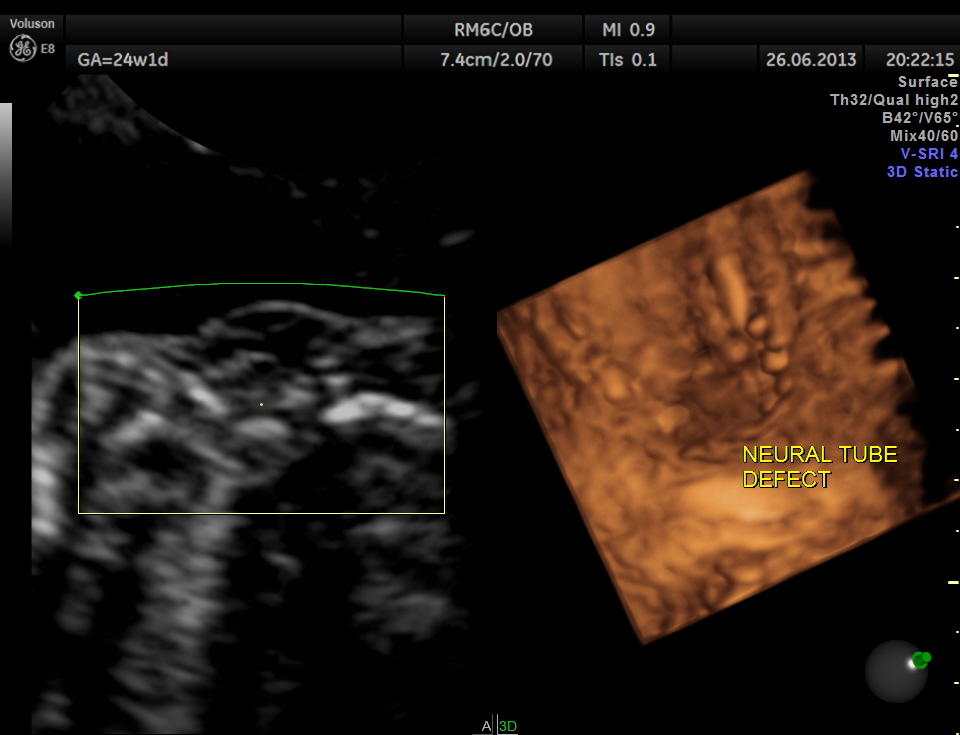

the next is a 3 d image of the open neural tube defect in the thoracic region

the following images are reconstructed images.